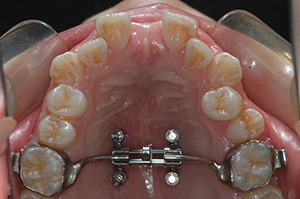

对于生长发育高峰期之前的青少年,一般会采用“牙支抗扩弓”的方法,对牙齿施力,使牙齿在牙槽骨里移动,并通过牙齿引导上颌骨中间的骨缝“打开”,从而实现“骨性扩弓”的目的。

但对于生长发育后期或成年患者,采用“牙支抗”的方式,效果就非常有限了。有些牙弓特别狭窄的患者只能等到成年后,通过外科手术的方式将已经闭合的上颌中缝劈开,再配合正畸扩弓。很多患者和家属都觉得“动刀太受罪,凑合凑合得了”。

2013年贾海潮在美国加州大学洛杉矶分校做访问学者,正好有老师在做“种植钉辅助支抗扩弓”方面的研究——在上颌植入几颗小小的微螺钉,就可以直接在骨头上施力“扩弓”。以往需要外科手术才能解决的问题,在牙椅上就能实现,贾海潮觉得这个方法对临床很有用。

学到了这个“对临床很有用”的技术,贾海潮回到祖国。2014年国内还没有这方面的器械,他和技工中心的技师合作定制,开始进行探索研究。

随着国际学术交往和技术的进步,2017年起“种植钉辅助支抗扩弓”相关的材料、器械被引入国内,逐渐为广大正畸医生了解、掌握,临床应用也越来越广泛。特别是近年来,“种植钉辅助支抗扩弓”方面的研究逐渐成为国际正畸学研究的热点之一。2018年,贾海潮获得2项实用新型专利。

2021年,贾海潮以第一作者和通讯作者的身份,在该期刊发表了研究论文,采用随机对照试验,揭示了种植钉辅助上颌快速扩弓治疗效果更好,副作用更小,是生长发育后期更好的扩弓方法。

讲起临床研究,贾海潮如数家珍。60例随机对照试验,在口腔正畸临床研究中无疑是一个大样本研究,30例使用种植钉辅助上颌快速扩弓,30例采用传统的牙支抗扩弓,长达4年多的病例收集,每一个病例都亲自测量、亲自记录。正是这样扎实的临床研究,赢得了国际评委们的认可。

十年来,贾海潮已累计完成种植钉辅助支抗扩弓300余例,年龄最大的患者42岁,以往需要外科手术才能解决的问题,通过4个直径不到2毫米的微螺钉就能解决,对于医生和患者都是更好的选择。